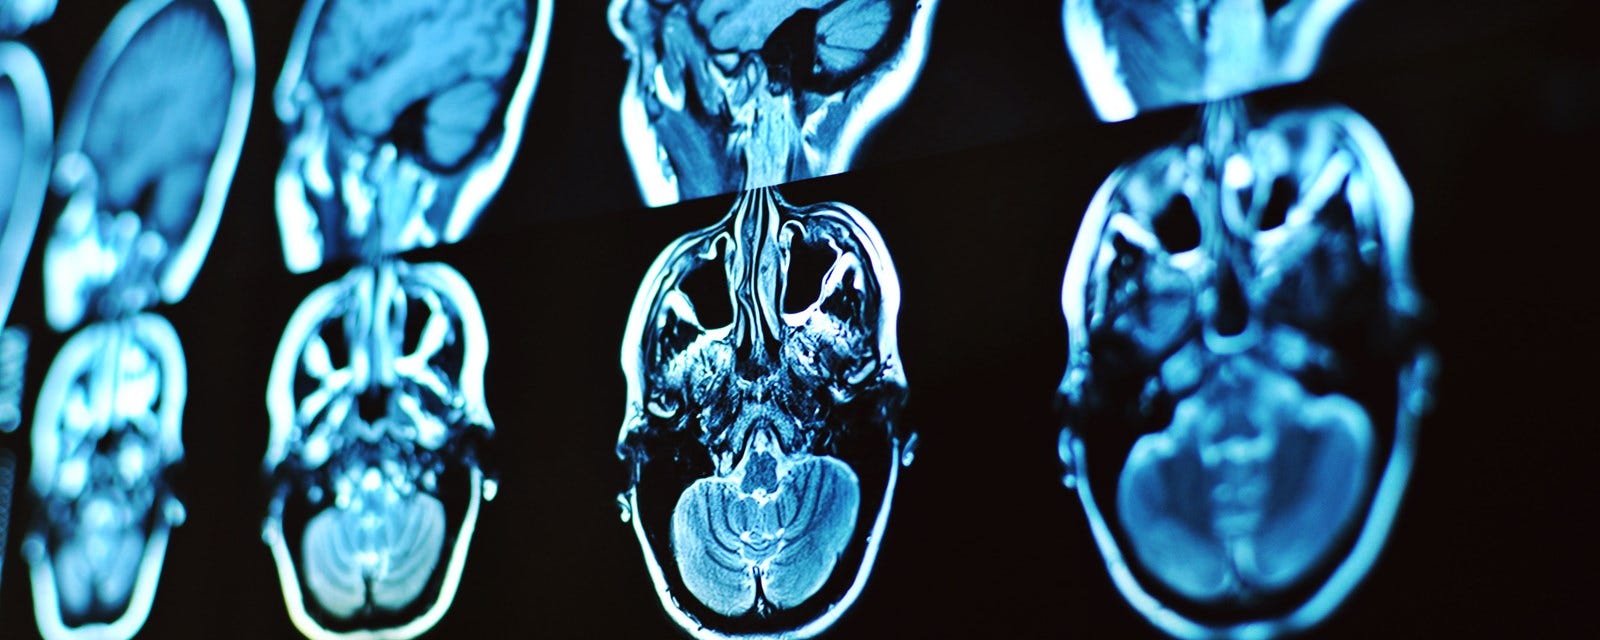

Prof dr beyin cerrahi. İlk ve ortaokulu ankara da tamamlanan yaşargil ankara. Hakan sabuncuoğlu değerli hastalarımız beyin cerrahisi tam olarak kullanılan adıyla beyin ve sinir cerrahisi nöroşirurji beyin omurilik ve periferik sinirlerin cerrahi hastalıkları ile ilgili ana bilim dalıdır. 01 gamma knife icon beyin hipofiz tümörlerinin ve damar hastalıklarının tedavisinde kullanılan bir ışın cerrahisi sistemidir. Beyin tümörlerini diğer organlarımızdki kanser gibi değerlendirmiyoruz.

Genel mikronöroşirürji merkezimizde cerrahi tedavi gerektiren tüm beyin omurilik ve sinir hastalıklarının cerrahi mikroskop ve yüksek teknolojinin sağladığı imkanlar kullanılarak ameliyatlarının gerçekleştirilmesi ameliyat sonrası yoğun bakım ünitesinde tedavisi ve. İstanbul marmara üniversitesi nde prof. Beyin ve sinir cerrahisi nöroşirürji bölümümüzde. Tanı ve tedavisi yapılan hastalıklar.

1925 yılında diyarbakır ın lice ilçesinde dünyaya gelen prof. Beyin omurilik ve sinir cerrahi uzmanı beyin ve omurilik tümörleri bel ve boyun fıtığı omurilik ve kafa travmaları beyin kanamaları beyin damar tıkanıkları omuriliği ve beyni besleyen damarlara oluşmuş anevrizmalar gibi hastalıkların tanısı ve tedavisiyle ilgilenir. Eski zamanlardan beri insanoğlunun günlük yaşantısını etkileyen ağrılı bir hastalık olarak medikal ve cerrahi birçok yöntem ile tedavi edilmeye çalışılmıştır.